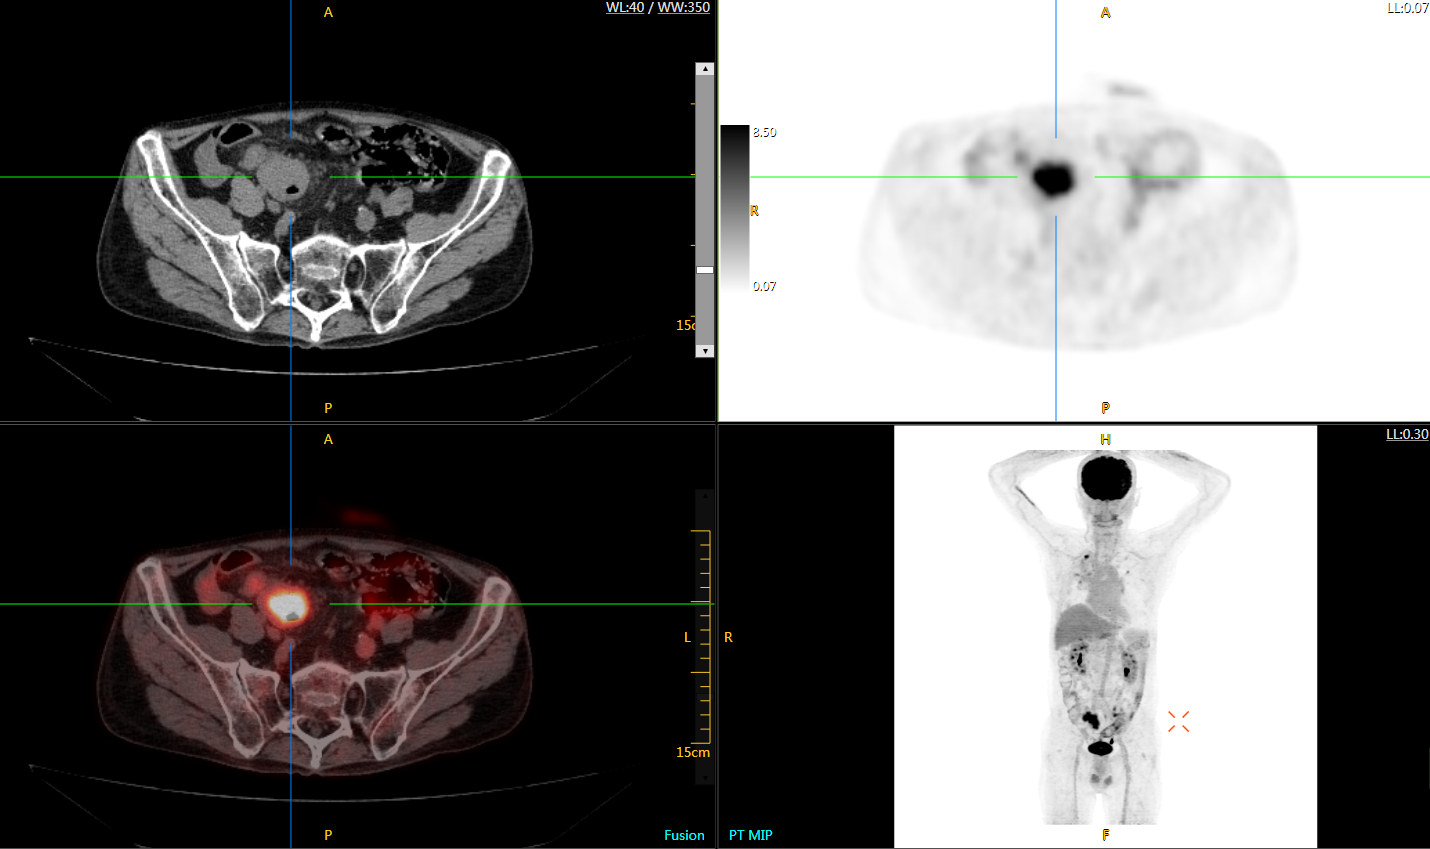

uExplorer探索者不再局限于傳統(tǒng)靜態(tài)代謝過程3D成像,而是在此基礎(chǔ)上新增一個維度——時間,從而實現(xiàn)4D全景成像。

注射總劑量為7.8mCi,14分鐘全身采集時間,在擁有超高靈敏度與超高分辨率的uEXPLORER上,即可得到展示顯示人體諸多精細(xì)結(jié)構(gòu)的高清三維圖像。

注射總劑量為7.8mCi,注射后1.6小時,基于uEXPLORER探索者掃描1分鐘的圖像

注射總劑量為0.67 mCi FDG(低于常規(guī)劑量的十分之一),基于uEXPLORER探索者掃描15分鐘的圖像

注射總劑量為6.9mCi,注射后10小時,基于uEXPLORER探索者掃描14分鐘的圖像